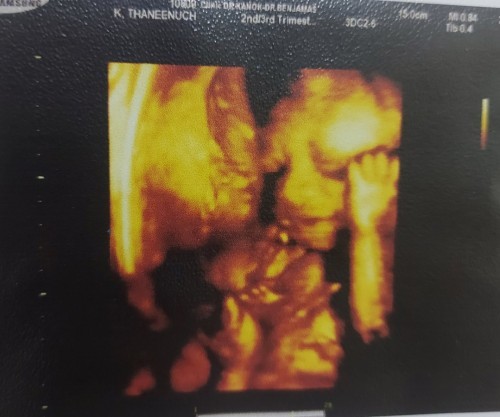

กติกาคือ ... 1️⃣ กดเข้าร่วมกิจกรรม และทำตามเงื่อนไขทุกข้อได้ที่ https://community.theasianparent.com/contest/1/1282?lng=th 2️⃣ โพสต์ภาพเจ้าหนูน้อยที่คิดว่าน่ารักที่สุด! (สามารถเป็นเจ้าหนูน้อยที่ยังอยู่ในท้องได้) ที่ใต้โพสต์นี้เลย 👇👇👇 💢 ย้ำ!! อย่าลืมทำการแชร์โพสต์กิจกรรมนี้ลงเฟสบุ๊คของคุณด้วยนะคะ! (ถ้าไม่มี แอดตัดสิทธิ์ทันทีน๊า) ⏳ ระยะเวลาร่วมกิจกรรมวันนี้ ถึง 30 พฤศจิกายน 2564 #TAPAppTH #TAPContestTH